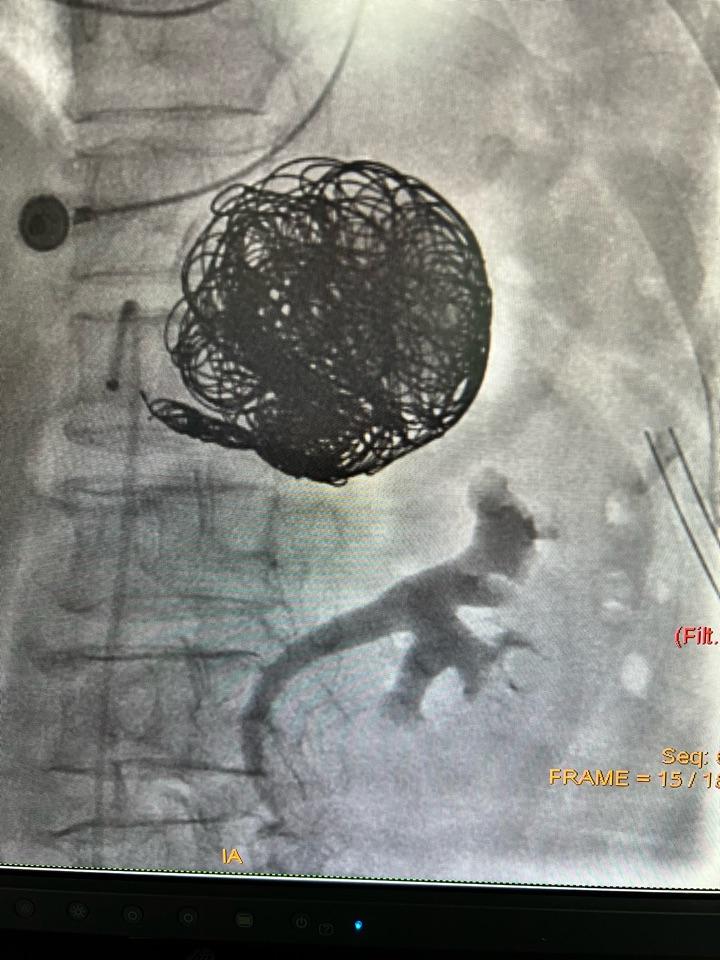

罕见的巨大脾动脉瘤的弹簧圈栓塞术

老年女性,做胆囊手术前发现脾动脉巨大动脉瘤,最大直径为8cm~7cm,转入我科急诊处理。

局麻微创行脾动脉瘤弹簧圈栓塞术,手术顺利,费时1小时,危机解除,患者卧床24小时后,顺利出院。